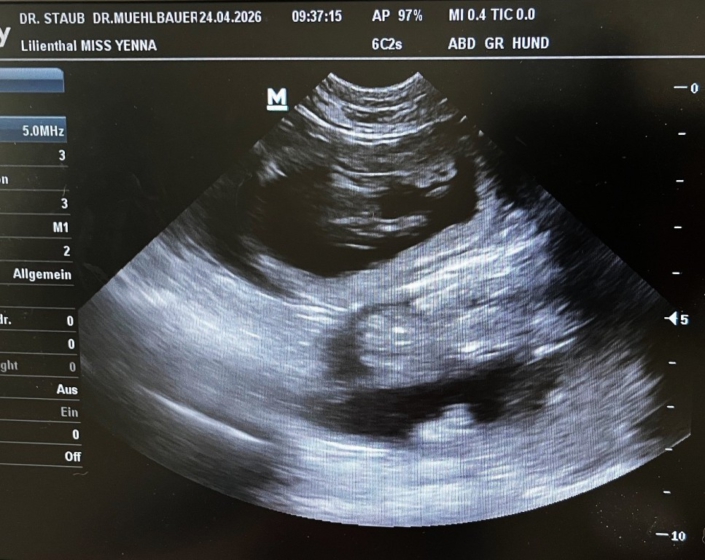

Das Bäuchlein wächst…..